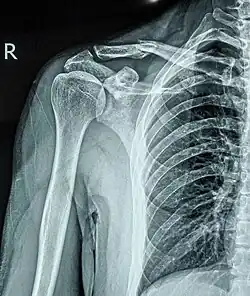

Перелом ключицы — патологическое состояние, проявляющееся нарушением анатомической целостности ключицы. Чаще всего переломы происходят в средней трети на границе наружной и средней третей ключицы, на наиболее изогнутой и истончённой её части. Наиболее часто встречающиеся — косые и оскольчатые.

Составляет 2,6-12 % от всего числа переломов, 44-66 % переломов плечевого пояса. В 80 % случаев перелом происходит в средней трети, 15% — перелом акромиального конца ключицы, 5 % — стернального (грудинного).

Переломы средней трети ключицы распространенная травма, составляющая от 2 до 5% всех переломов, от 35 до 45% повреждений верхних конечностей. Согласно результатам различных биомеханических исследований, средняя треть —наиболее слабое место ключицы, с чем связана высокая частота переломов этой локализации[1].

Локальная болезненность, припухлость, деформация, кровоизлияние и укорочение надплечья, плечо опущено и смещено кпереди. Периферический отломок вместе с верхней конечностью под влиянием её тяжести и сокращения большой грудной и подключичной мышцы смещается вниз, вперёд и внутрь. Центральный отломок под воздействием грудино-ключичной мышцы смещается кверху и сзади. Отломки сближаются и заходят один на другой.

Выполняется рентген в прямой и боковой проекциях.